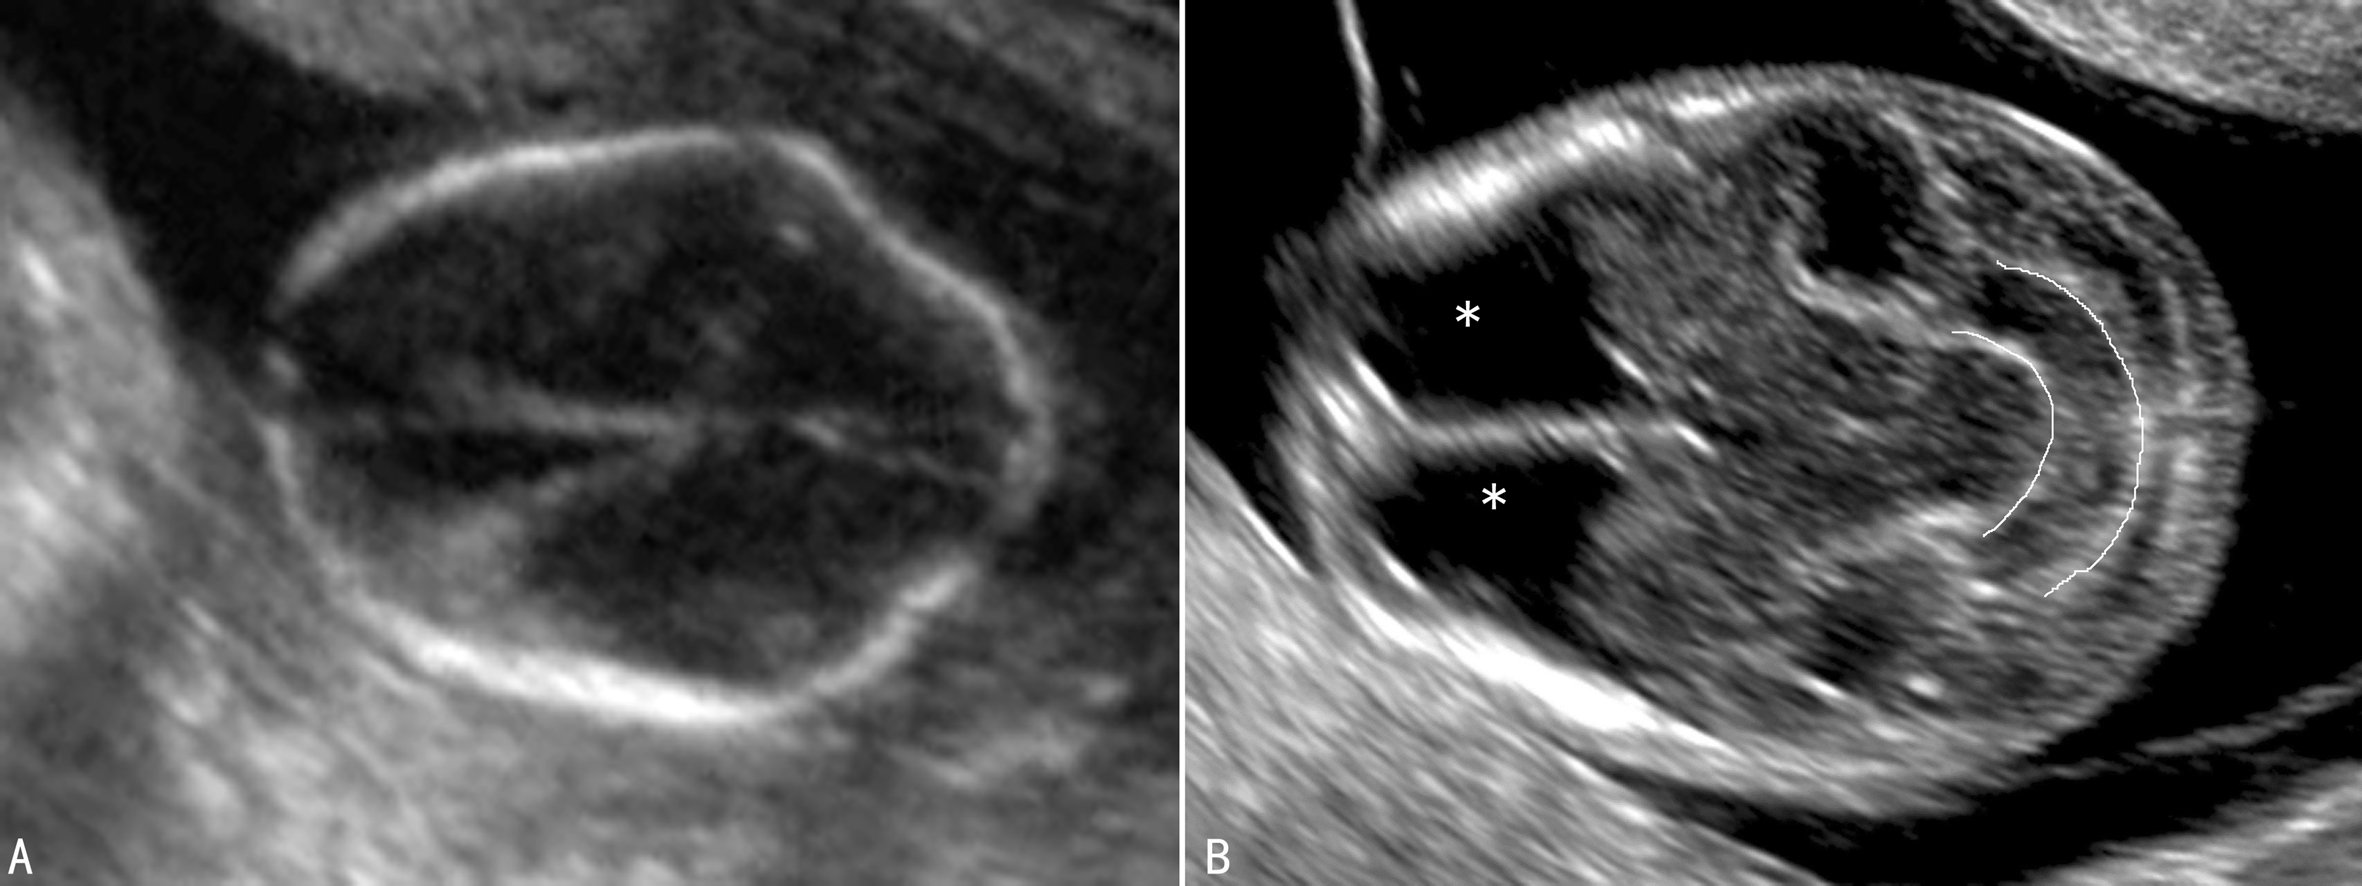

脊柱裂、脊髓脊膜膨出可引起颅内压力减低,胎儿颅骨内陷,显示双侧颞部向内凹陷,额部隆起,形成柠檬状头型(图2A),称为“柠檬征”;妊娠中晚期伴随颅骨钙化、颅内脑组织的生长支撑了颅骨可改变柠檬状头型,颅骨恢复正常形态,“柠檬征”逐渐消失;另外,小脑也会因同样的原因向枕骨大孔方向突出而呈香蕉状(图2B),称“香蕉征”;同时出现第四脑室、小脑幕及延髓移位,后颅窝池消失。

图2 开放性脊柱裂头型及小脑继发性改变